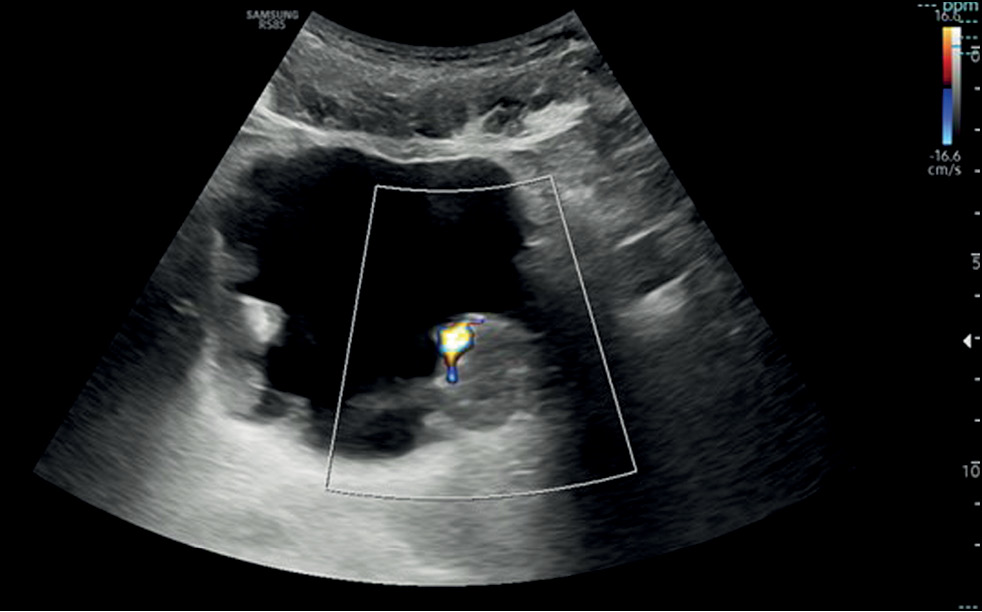

The bladder wall appears as layered with the hypoechoic muscle between two hyperechoic layers corresponding to the serosa and mucosa. The lateral and posterior walls are well visualized in US, and the anterior wall is affected by the reverberation phenomena, which can be adjusted with the time–gain compensation. To selectively explore the anterior wall and the vesical cupola, the examination can be performed using a higher-frequency linear transducer (>7.5 MHz). To evaluate the ureteral jet, which is a normal and periodic efflux of urine from the ureter into the bladder, color Doppler is necessary for the trigone of the posterior wall to exclude a complete ureteral obstruction.

If a focal mass is detected in the US image, the presence of additional lesions must be further explored, considering that one-third of tumors are multifocal, and an additional evaluation with Doppler that helps in identifying the internal vascularity with a rich blood flow signal or a stellate morphology and differentiating a potential tumor from a blood clot. The latter can be excluded by asking the patient to change position from supine to lateral to assess for lesion mobility typical of a clot or performing bladder irrigation, followed by another US scan [11] (Fig.1).

Fig. 1. Transverse ultrasound image of the bladder showing diffuse irregular wall thickening with multiple masses and endoluminal development. Color Doppler on the largest echogenic lesion, localized on the left posterior bladder wall, showed vascularity within the mass.